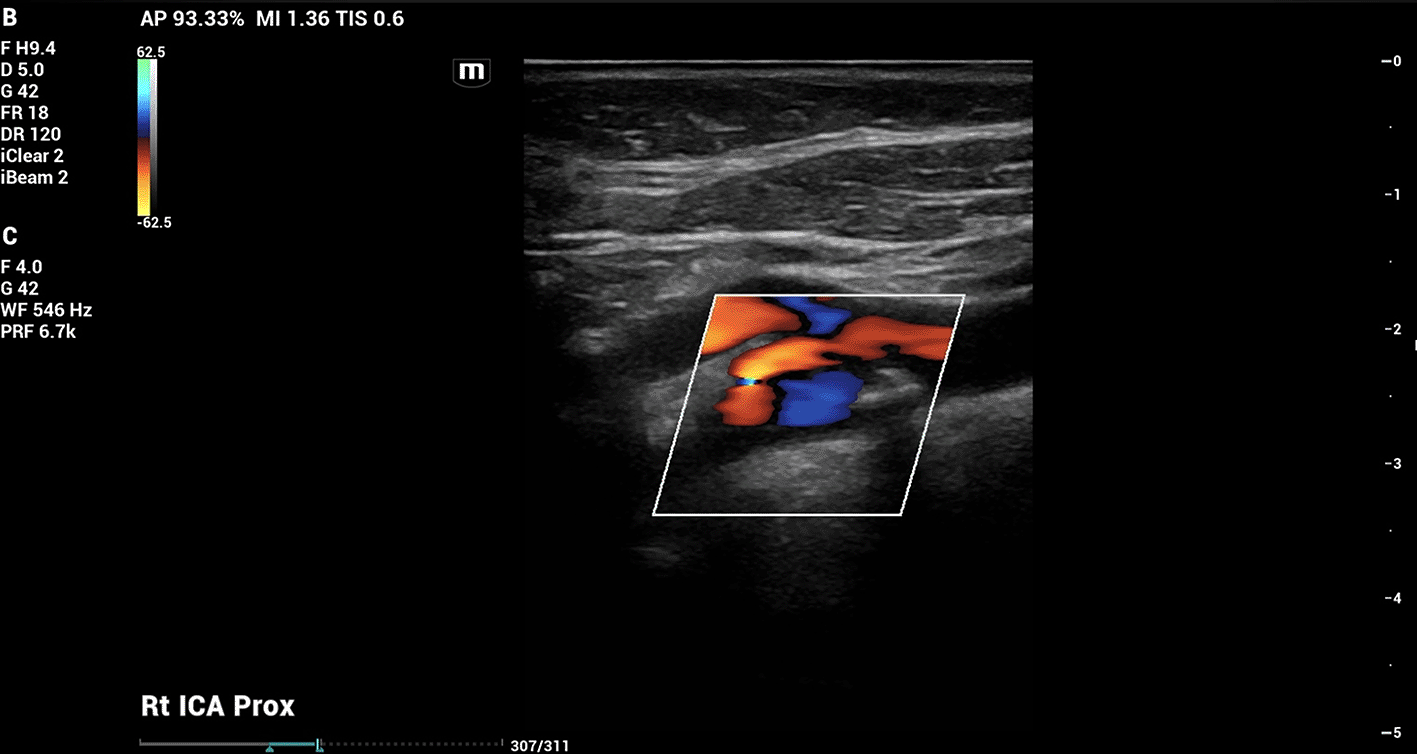

On doppler imaging study, all vessel velocities measured by carotid duplex were significantly higher on the right side than the left. The measured peak velocity of the right internal carotid artery (ICA) was 122.02 cm/s, the external carotid artery (ECA) 118.45 cm/s, and the common carotid artery (CCA) 98.81 cm/s. The left sided measured peak velocities were the ICA of 47.33 cm/s, the ECA of 75.59 cm/s, and the CCA of 68.88 cm/s. In addition, the vessel velocity difference was greater in the ICA at 74.69 cm/s, than in the ECA (42.86 cm/s) or the CCA (29.93 cm/s). The carotid duplex interpretation concluded 50% stenosis in the right ICA ( Figure 2) with heterogenous calcified plaquing and minimal stenosis on the left. The patient was therefore referred for further vascular evaluation.